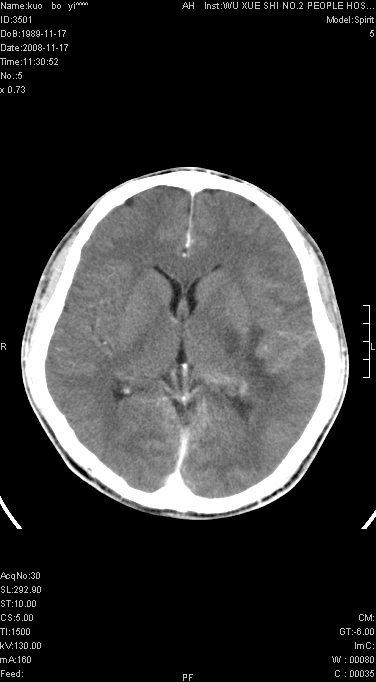

右侧肢体无力一周

这么大片面积,中线居中,占位效应不明显,考虑脑梗塞。

灶中央有厚环状高密度成分,顶叶皮质局部有显著的受压表现,多支持占位性病变,胶质瘤?淋巴瘤?转移?不知患者年龄多大,病史较短,不除外炎性

左顶叶较大范围水肿区,内见明显强化的片状 棉絮状组织,但占位效应不明显。多考虑:脑炎!